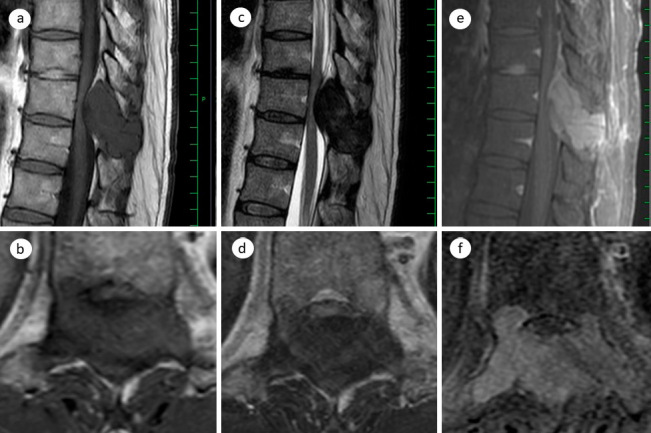

A Case of Desmoplastic Fibroma of the Thoracic Spine with Incomplete Paralysis of both Lower Limbs.

胸椎结缔组织增生纤维瘤伴双下肢不完全瘫痪1例。